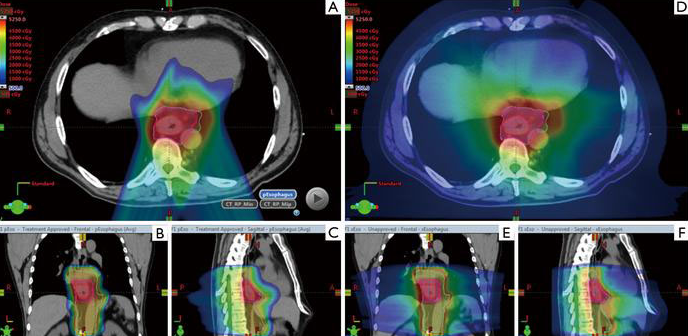

因此,質(zhì)子治療憑借特殊的“布拉格峰效應(yīng)”,為食管癌的治療提供了便利。與光子放療相比,質(zhì)子治療可以減少心肺等風(fēng)險(xiǎn)器官的輻射劑量,降低并發(fā)癥,同時(shí)無(wú)需降低針對(duì)腫瘤的輻射劑量,提高食管癌的治愈率。

▲質(zhì)子治療食管癌,